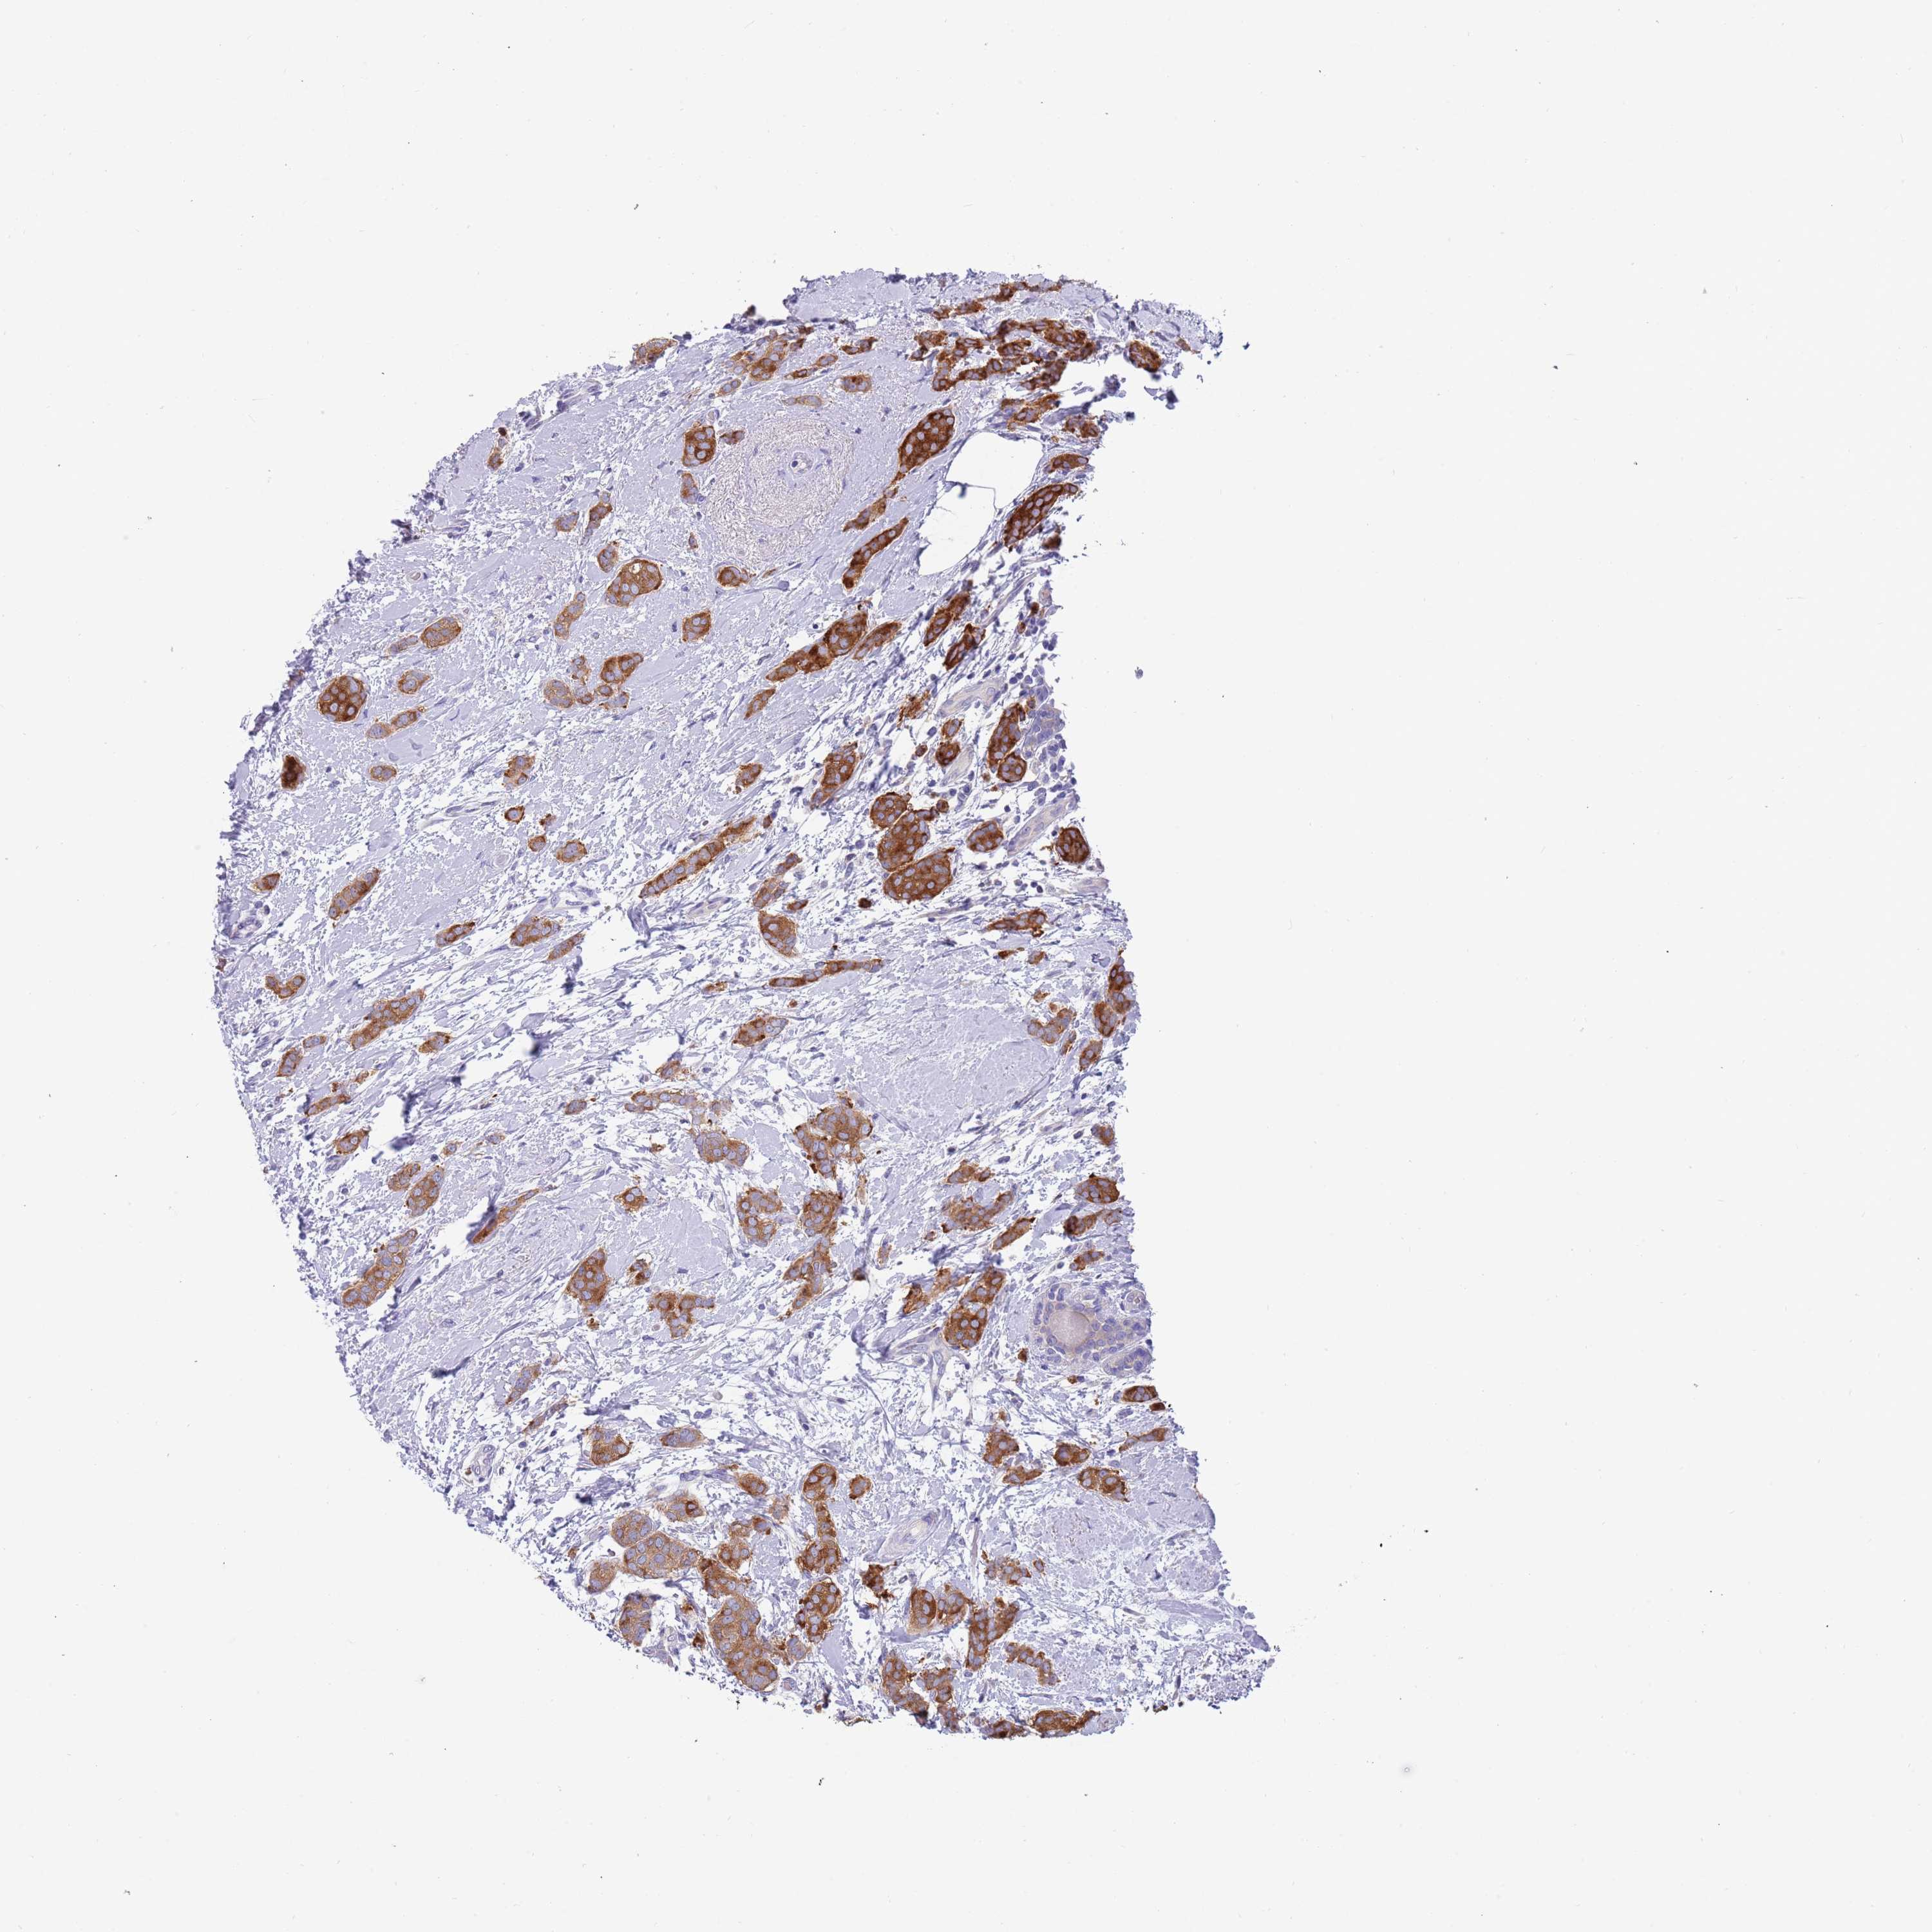

CANCER BREAST CANCER Show tissue menu

BRCA TCGA BRCA VALIDATION PROTEIN EXPRESSION